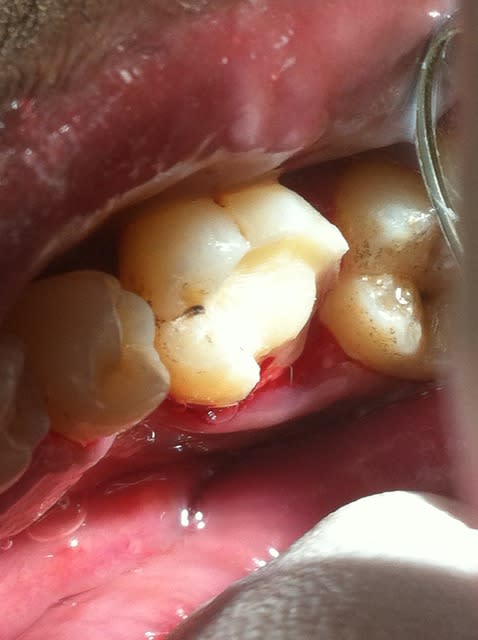

Onlay emax à 5 ans... contrôle la semaine dernière...

Dans cette situation, que donnerait un composite ?

tiens c'est bizarre , sur la dernière photo de cingulum (magnifique travail d'ailleurs) , la dent est toujours sur l'arcade alors que le joint semble être juxta voir sous gingival. Il m'a semblé avoir lu plus haut qu'un joint en compo ça se carie automatiquement au bout de cinq ans....

Allez cingulum , arrête de nous faire marcher, fais peter la radio avec la reprise de carie, l'endo, l'IC et la CCM!

C'est très beau...

Mais je dois admettre que dans ce cas... Des IC-CCM aux limites un peu sous-gingivales qui tiennent 30 ans on en voit aussi. Dans ce cas précis je ne suis pas certain que ce soit préférable (collage), que se passera-t-il si reprise de carie? La limite sera très certainement trop sous gingivale et la couronne ne sera probablement pas réalisable (même si c'est au bout de 15 ans). Vu le reste à charge supérieur et la forte probabilité d'avoir à extraire en cas d'échec, ne valait-il pas mieux utiliser une technique pour laquelle on a énormément de recul?